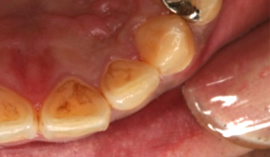

う蝕検知液を使った治療例

むし歯検知液で染めだされたむし歯

う蝕検知液で染めだされたむし歯

注:濃いピンク色の部分